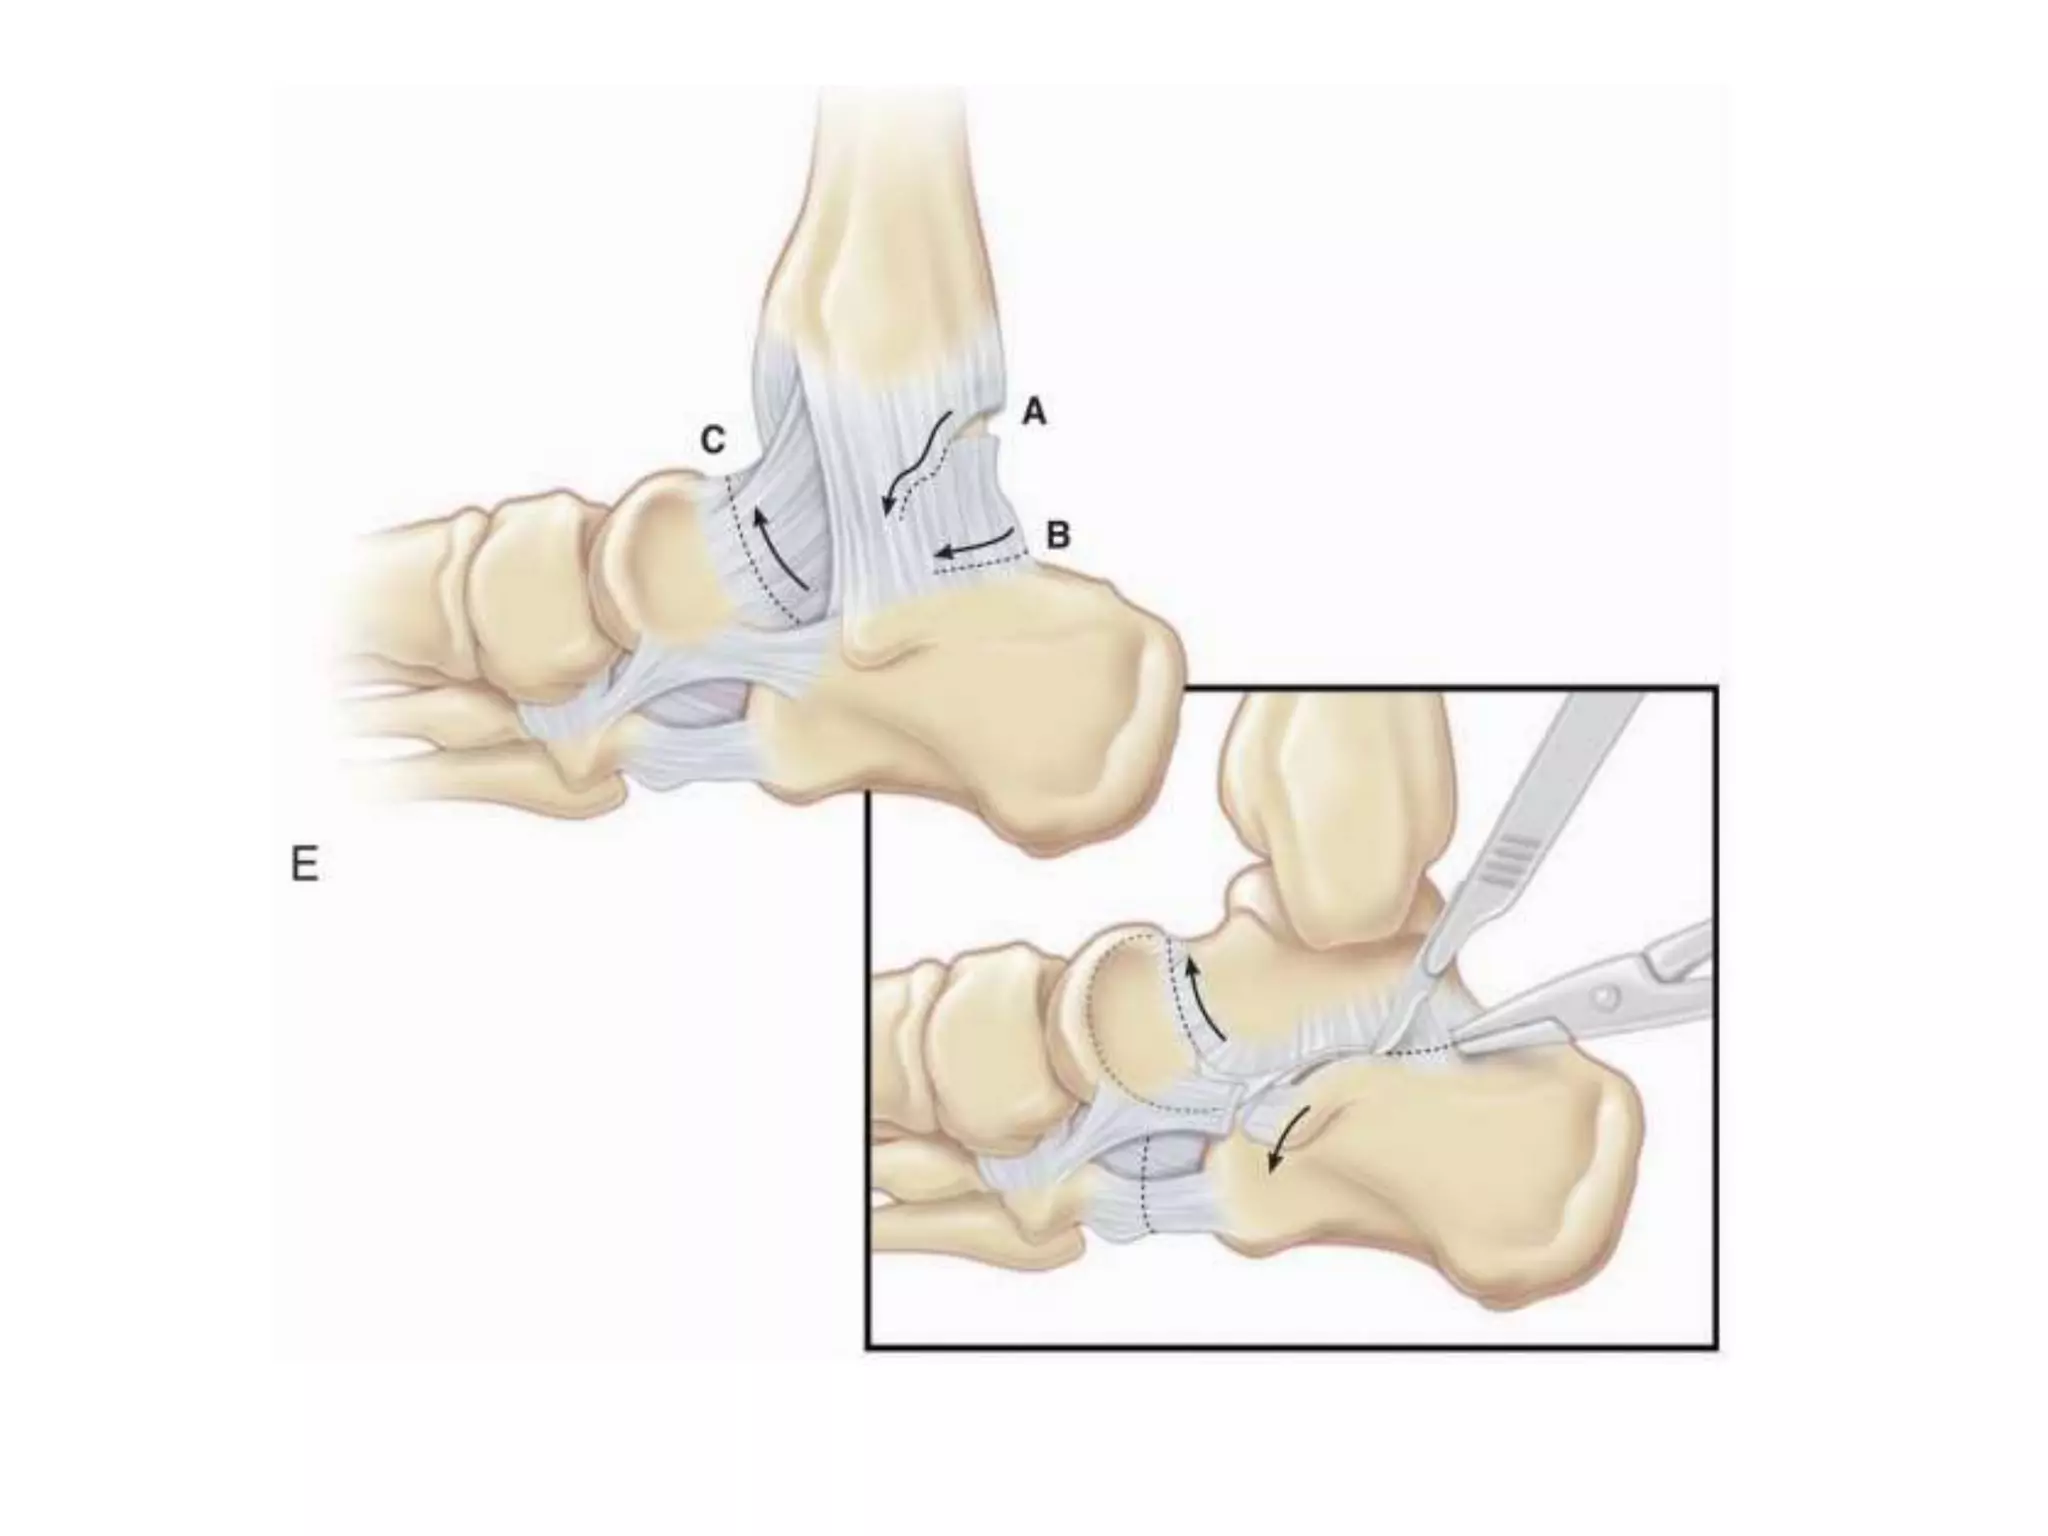

TENDON TRANSFERS

• INDICATION –PASSIVELY CORRECTABLE FOOT

RESULTING FROM MUSCLE IMBALANCE.

• NEVER A PRIMARY PROCEDURE

• THREE TYPES-

• 1.TIBIALIS ANTERIOR

• 2.TIBIALIS POSTERIOR

• 3.SPLIT ANTERIOR TIBIALIS TENDON

TRANSFER

TIBIALIS ANTERIOR TRANSFER

• Indicated when there is dynamic inversion or

supination of the midfoot, especially in swing

phase.

• The goal is to eliminate the supinated

position for the initiation of stance.

• Split transfer-lateral arm reinserted in the

cuboid or lateral cuneiform.

• Entire tendon transfer-the insertion should

be moved to the midline or just slightly

lateral to midline.

• Anterior tibialis transfer with lengthening-as

part of revision for a postoperative dorsal

bunion when the first ray is excessively

dorsiflexed